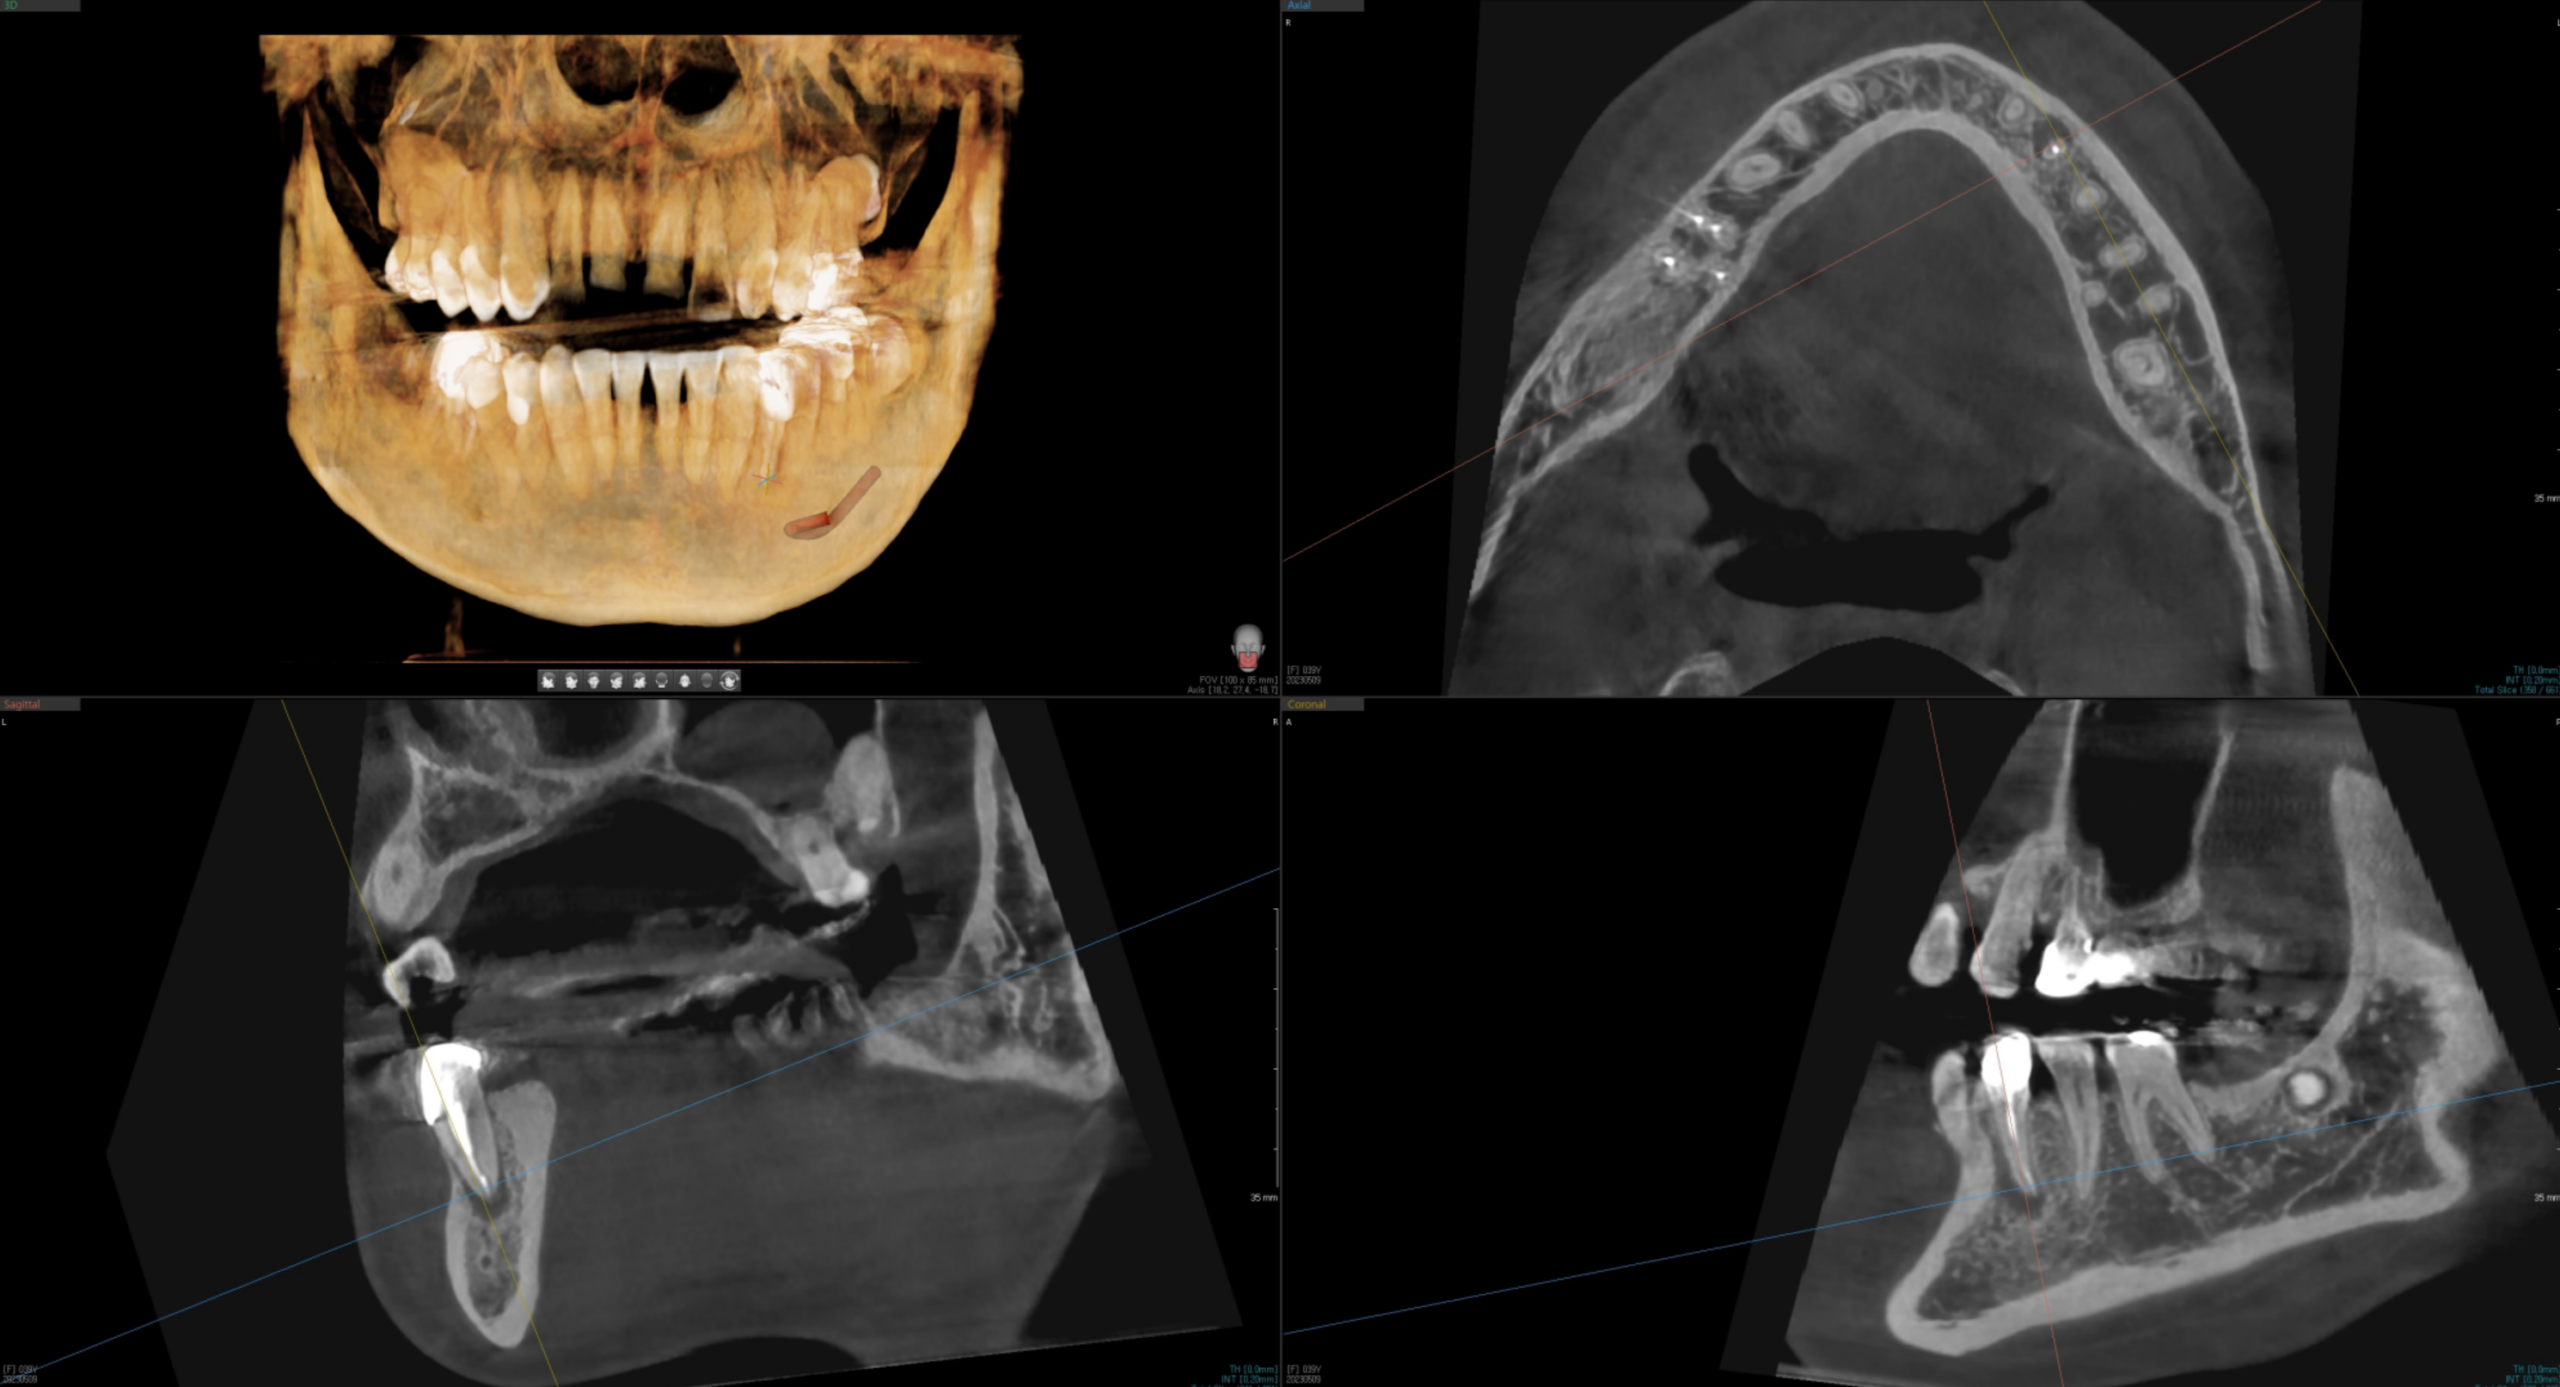

저는 경사 식립 케이스에서 반드시 CT 기반 3D 시뮬레이션을 선행합니다.

임플란트의 장축 방향, 보철물 수직 공간, 인접 구조물과의 안전 거리를

입체적으로 계산한 뒤, 서지컬 가이드를 활용해

계획된 각도를 수술실에서 정확히 구현합니다.

‘감’이 아니라 계획이 먼저입니다.

수직 식립 불가 케이스에서의 경사 식립 적용 원리

신경·상악동 손상 위험이 있거나, 뼈 이식 없이는 원하는 길이 확보 불가.

각도를 활용해 뼈량이 풍부한 부위에 고정. 상악동·신경과 안전 거리 자연스럽게 확보.

다이어그램은 원리 이해를 위한 개념도입니다. 실제 식립 각도는 CT 분석 결과에 따라 개인별로 다르게 결정됩니다.